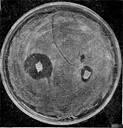

Рис. 1. Синергізм у мікробів. Навколо агарового блоку з культурою актиномпцета видна зона стимуляції росту цвілевого гриба.

Рис. 2. Приклад антагонізму в мікробів. Видна зона придушення росту стафілококу навколо агарового блоку з культурою актиноміцету.